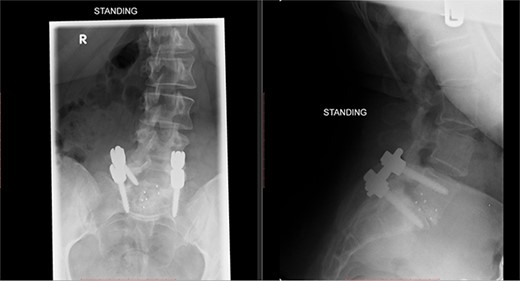

Postoperatively, the patient developed severe radiculopathy down the left leg and required opiates. The patient could not move the left leg and was unable to mobilize. X-rays showed the implants were in position (Fig. 3), but the information from a fresh MRI scan was limited due to metal artefact (Fig. 4). With ongoing, unrelenting pain, she was returned to theatre on the fourth postoperative date, and the wound was re-explored. Intraoperatively, no dural tear was identified, the nerve roots were free, and the screws appeared in position. She was then discharged home after ten nights in hospital, instead of the standard three nights that would be common practice.

Postoperative X-ray of the lumbar spine performed in January 2017, showing the implants in place.